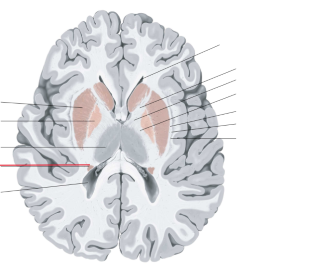

nucleus caudatus

putamen

globus pallidus

capsula interna (corona radiata)

capsula externa

capsula extrema

laterale ventrikels (I en II)

septum pellucidum